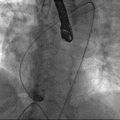

根部造影

导丝跨瓣

输送器定位

释放瓣膜

瓣膜释放完毕